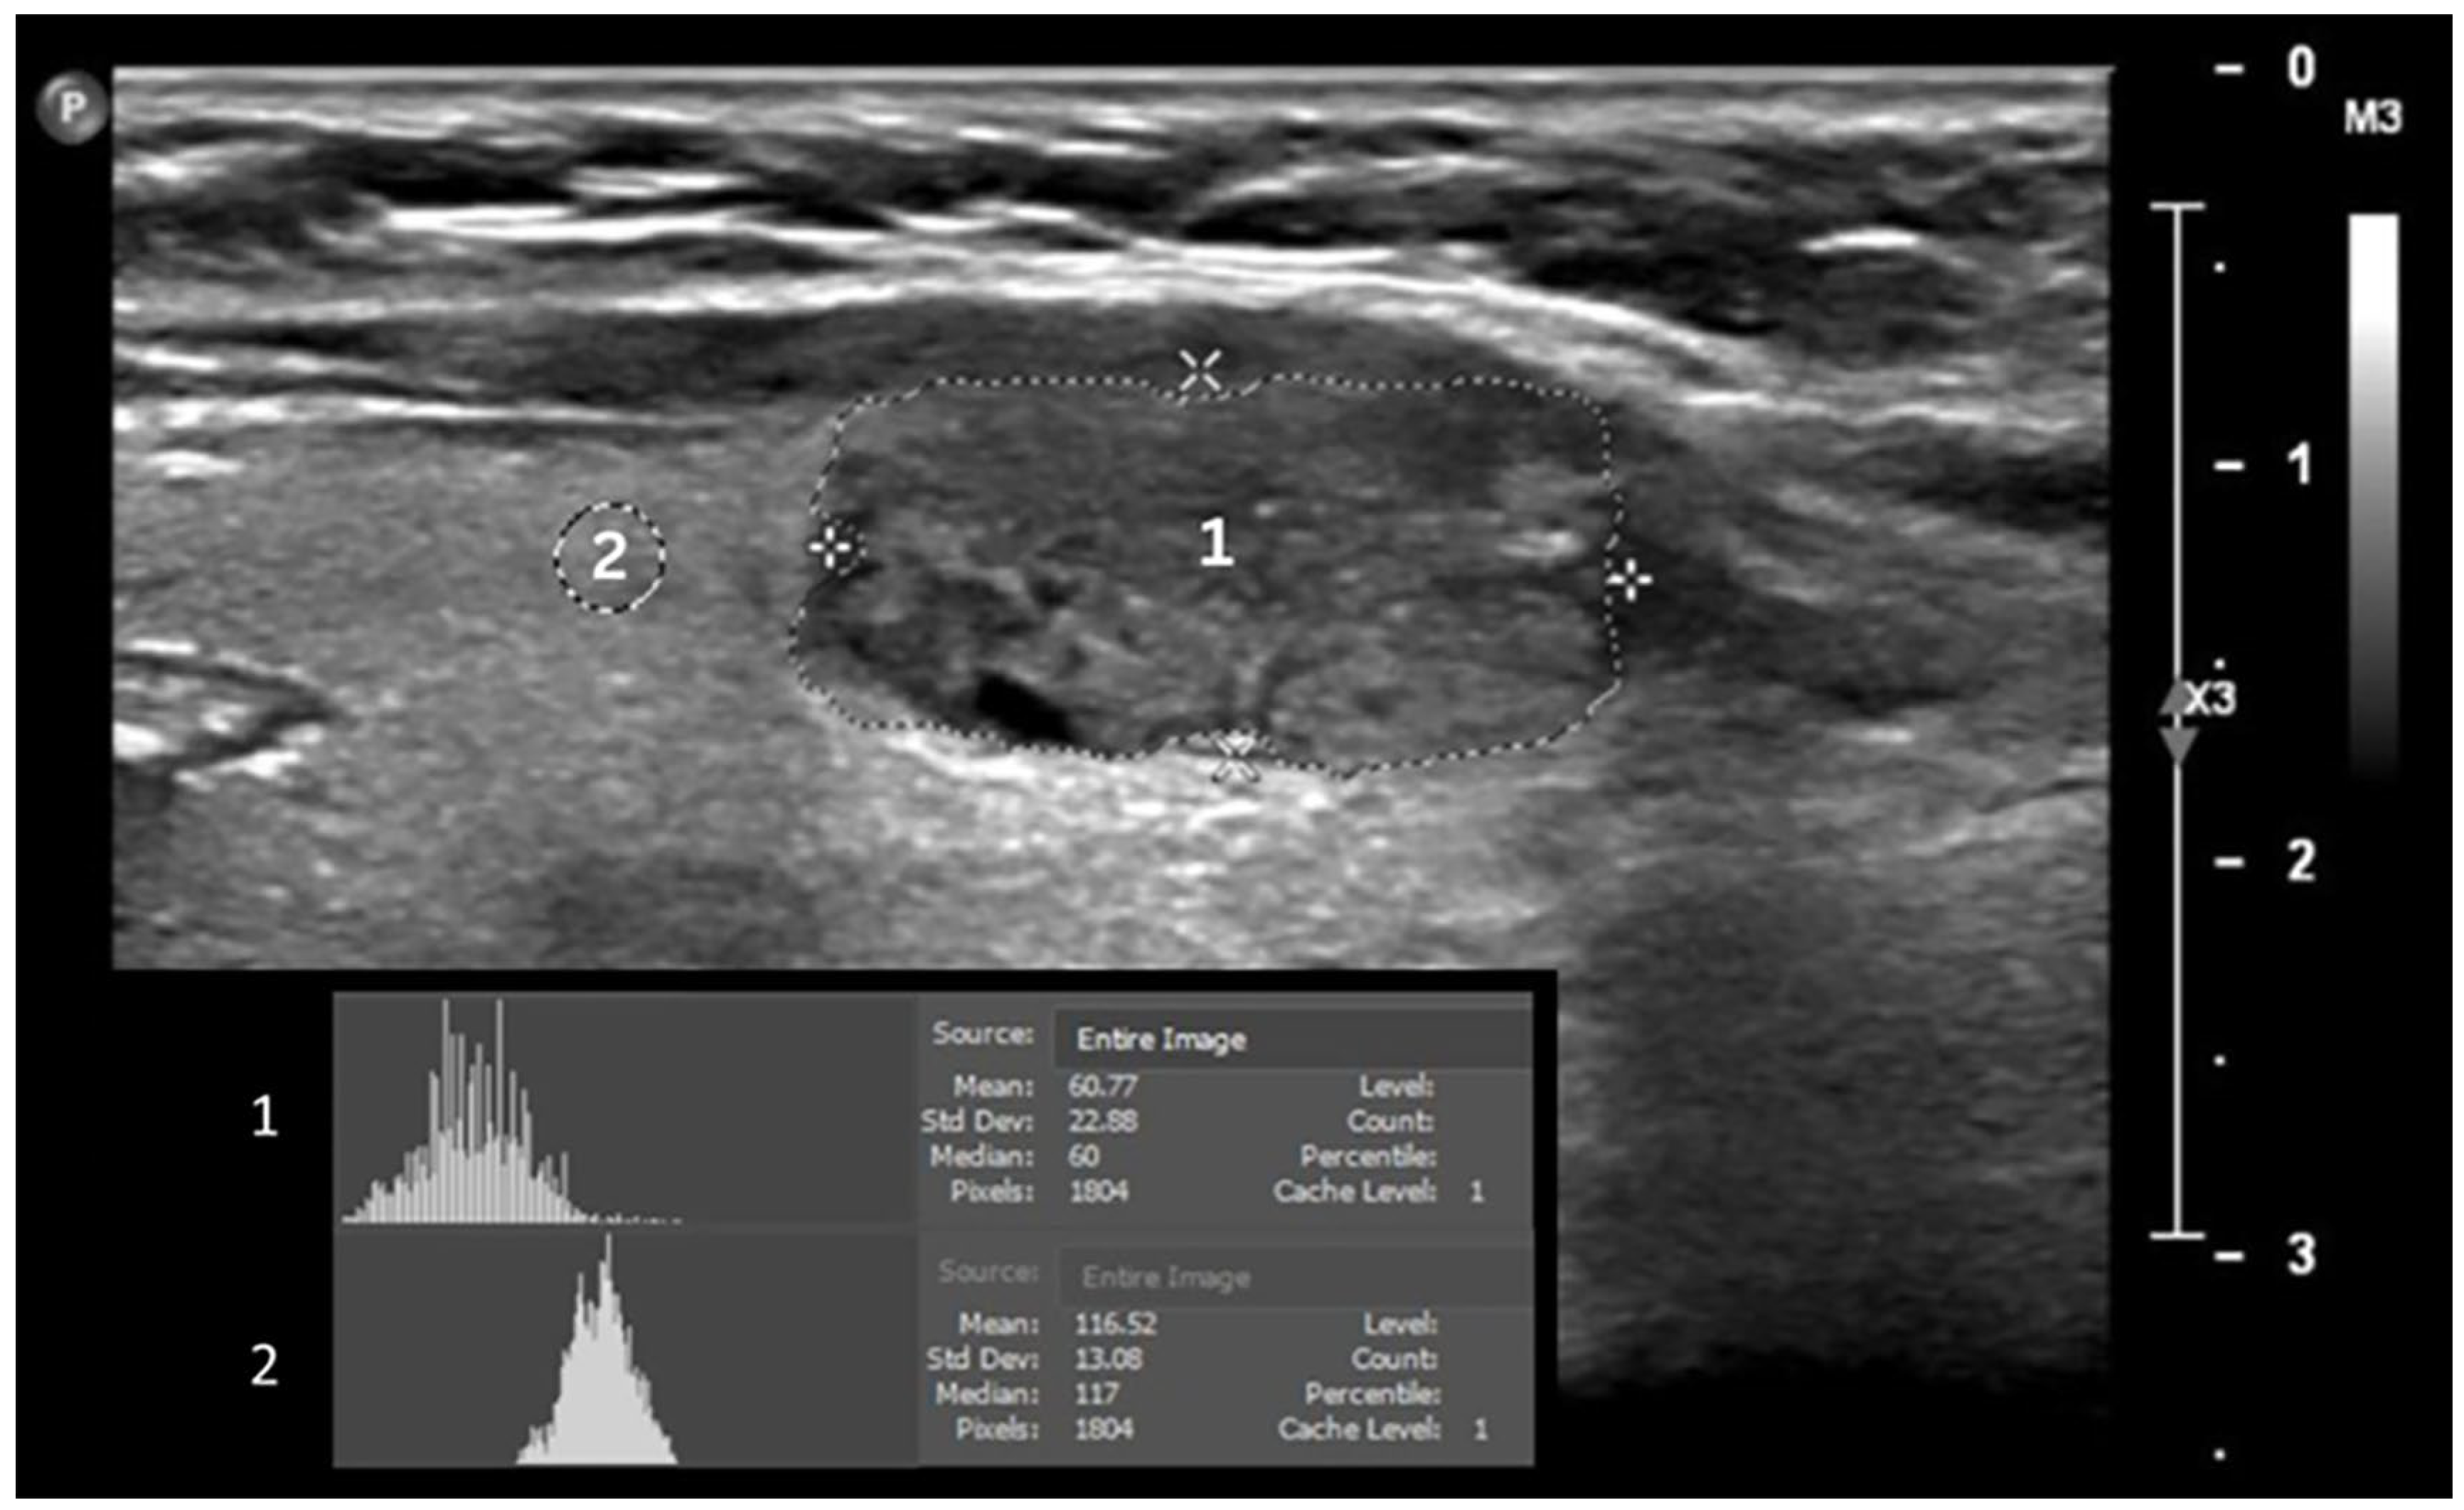

2.2. Data Acquisition and Ultrasound Image Analysis

- Harris-Love, M.O.; Seamon, B.A.; Teixeira, C.; Ismail, C. Ultrasound estimates of muscle quality in older adults: Reliability and comparison of Photoshop and ImageJ for the grayscale analysis of muscle echogenicity. PeerJ 2016, 2016, e1721. [Google Scholar] [CrossRef] [PubMed]

- Ikuta, E.; Koshiyama, M.; Watanabe, Y.; Banba, A.; Yanagisawa, N.; Nakagawa, M.; Ono, A.; Seki, K.; Kambe, H.; Godo, T.; et al. A Histogram Analysis of the Pixel Grayscale (Luminous Intensity) of B-Mode Ultrasound Images of the Subcutaneous Layer Predicts the Grade of Leg Edema in Pregnant Women. Healthcare 2023, 11, 1328. [Google Scholar] [CrossRef]

- Sabetai, M.M.; Tegos, T.J.; Nicolaides, A.N.; Dhanjil, S.; Pare, G.J.; Stevens, J.M. Reproducibility of computer-quantified carotid plaque echogenicity: Can we overcome the subjectivity? Stroke 2000, 31, 2189–2196. [Google Scholar] [CrossRef]

- Wu, M.H.; Chen, C.N.; Chen, K.Y.; Ho, M.C.; Tai, H.C.; Wang, Y.H.; Chen, A.; Chang, K.J. Quantitative analysis of echogenicity for patients with thyroid nodules. Sci. Rep. 2016, 6, 35632. [Google Scholar] [CrossRef] [PubMed]